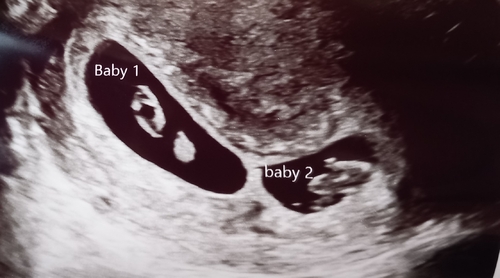

Daar zijn ze! Nu 9+4 weken. Vrijdag eerste termijn echo (10 weken).

Iken mijn man moesten even een week wennen aan het idee. Maar vandaag al heerlijk wat kleine kleertjes gekocht. Want maat 44 en 50 heb ik niet in huis van mijn vorige zwangerschap.

Onze dochter is tegen de tijd dat ze worden geboren met 5 geworden.